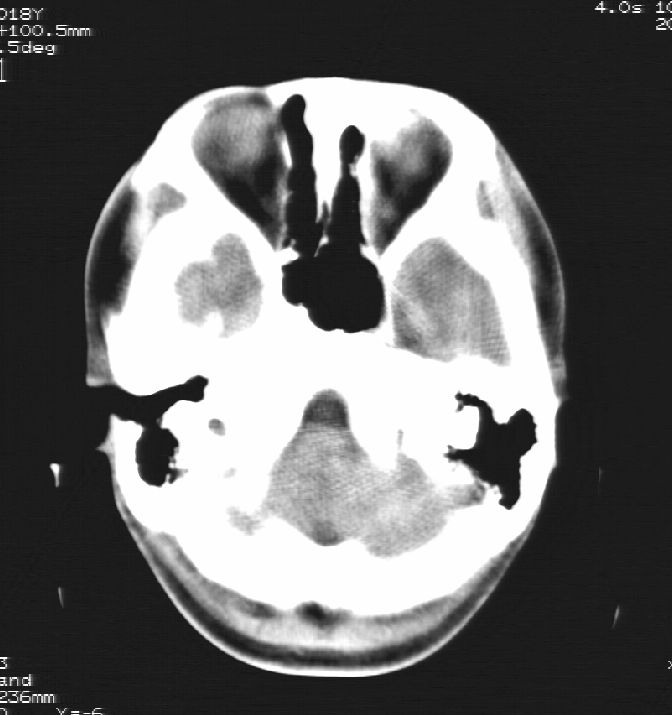

胼胝体发育不全合并 透明隔缺如 、脂肪瘤。

胼胝体发育不全合并脂肪瘤;建议必要时行mri检查。

脑水肿,头皮下血肿,胼胝体发育不全、合并脂肪瘤及钙化;建议必要时行mri检查。

胼胝体发育不全、合并脂肪瘤及钙化。